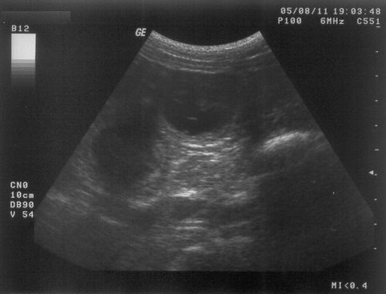

11.08.2005

So ... nun steht es definitiv fest (als ob ich es nicht schon die ganze Zeit gewusst hätte).

Ich bin schwanger und meine Welpen sollen im September (ca. 15.09.2005) zur Welt kommen.

Ein "bewegtes" Ultraschallbild findet ihr übrigens hier (Ladezeiten beachten und abwarten)

Anklicken (Ladezeiten beachten und abwarten)